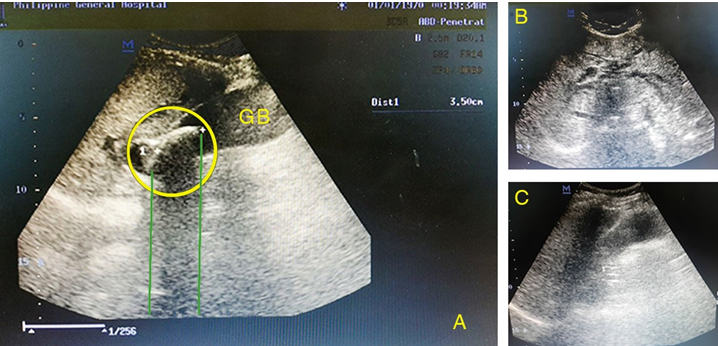

On presentation at the ED, she was alert, awake, coherent, tachycardic, normotensive, and afebrile. She had icteric sclerae (Figure 1) with right upper quadrant and epigastric tenderness. The rest of the examination was unremarkable. Initial laboratory report (Table 1) revealed leukocytosis, hyperbilirubinemia, elevated aminotransferases with normal prothrombin time, and electrolytes. Hepatitis titers were normal. The hepatobiliary ultrasonography (Figure 2) revealed a hydropic gallbladder with a 3.5 × 3 cm stone at the Hartmann’s pouch with markedly dilated intrahepatic ducts and common hepatic duct. The common bile duct (CBD) was normal at 0.6 cm. The patient was diagnosed as a case of obstructive jaundice secondary to MS with moderate cholangitis based on the Tokyo Guidelines 2018.

Figure 2: Hepatobiliary ultrasonography. (A) Revealed hydrops gallbladder with thickened walls (4 mm) and an impacted lesion (yellow circle) with posterior shadowing measuring (green lines) 3.5 cm at the Hartmann’s pouch. (B) Dilated intrahepatic ducts. (C) Thickened gallbladder wall (4 mm).

Consistent with literature review, the patient presented with obstructive jaundice (60–100%) accompanied with abdominal pain over the right upper quadrant (50–100%). The most common laboratory findings with MS patients are hyperbilirubinemia, elevated aminotransferase levels, and leukocytosis which are also seen in patients with cholangitis and cholecystitis [6]. The only adjunct imaging done for the patient was ultrasound which has a diagnostic accuracy of 29% [7] with sensitivity of 8.3–27% [8],[9]. The ultrasound image we obtained for our patient, with a demonstration of a stone in the neck, dilated common and intrahepatic ducts, and a normal sized CBD are diagnostic of MS. A magnetic resonance cholangiopancreatography (MRCP) or an endoscopic retrograde cholangiopancreatography (ERCP) would have been ideal to obtain a preoperative roadmap to better prepare the surgical team and simplify intraoperative decision making. Magnetic resonance cholangiopancreatography was not available during that time and endoscopy for this case was deemed not a priority by the endoscopists due to concerns for safety and allocation of limited instrumentation. Performance of a preoperative cholangiography may have obviated the need for intraoperative fluoroscopic imaging which consequently prolonged the surgery and added to the physical stress of the patient and the entire surgical team. It likewise consumed precious operating room time shared by all the surgical specialties during this crisis situation.